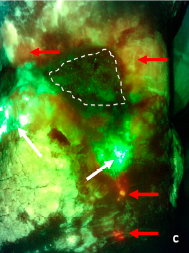

Skin Pigmentation Impacts the Clinical Diagnosis of Wound Infection: Imaging of Bacterial Burden to Overcome Diagnostic Limitations

Johnson J. et al. JREHD 2023

Bacterial Fluorescence Imaging to Address Racial Inequities in Wound Infection Assessment

Andersen, CA et al. Adv Skin & Wound Care 2024